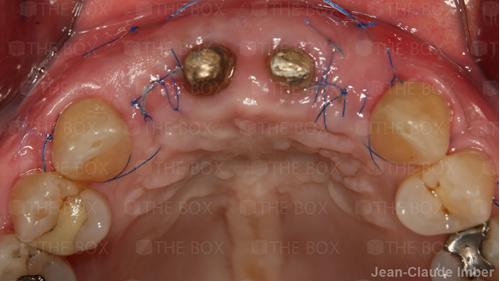

Infra bony defect one wall defect follow up 18 months show regeneration of buccal bone and interdental defect utilizing allograft bone substitute